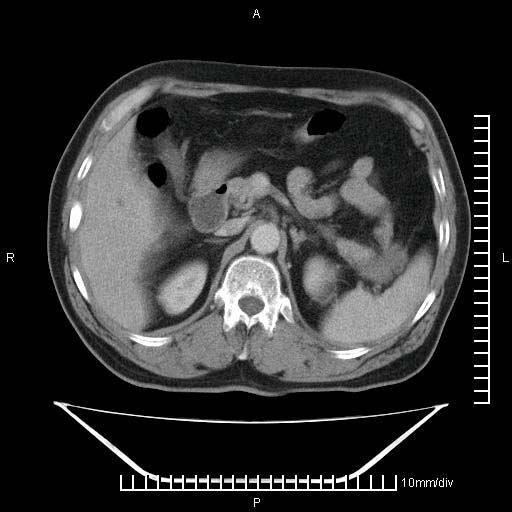

标题: CT25082:肝脏增强:男性,70岁 [打印本页]

标题: CT25082:肝脏增强:男性,70岁

患者以心脏疾病收住院,腹部无明显症状,b超查肝脏有占位。

肝内多发转移瘤,右下肺炎症并少量胸水。胃壁增厚建议胃镜,胰尾部“病变”为肠管。

1)肝脏多发性转移瘤(不排除胰尾癌转移所致可能)。2)腹水。3)右侧少量胸腔积液。

胰尾占位?结肠脾曲?

ct25082 结果:转移瘤

外院mr结果:胰尾恶性占位。